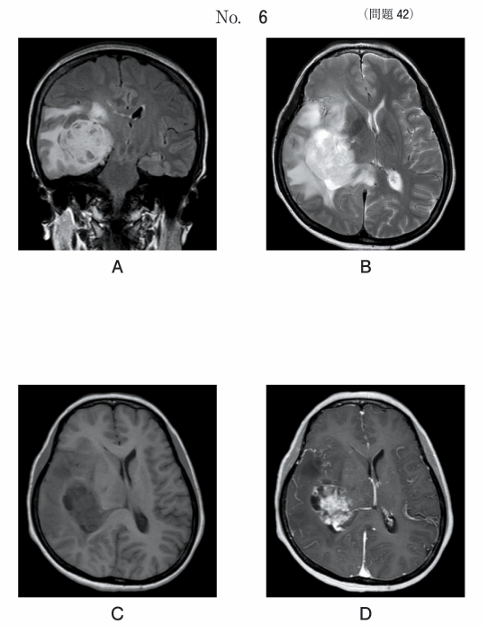

午前/問題42

MR像別冊No. 6A、B、C、Dを別に示す。正しいのはどれか。2つ選べ。

1.AはFLAIR像である。

2.BはT1強調像である。

3.CはT2強調像である。

4.Dは拡散強調像である。

5.Dは造影後の像である。